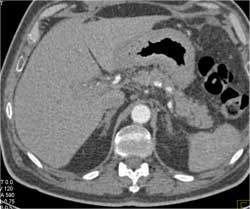

Gastric Cancer With Endoscopic View